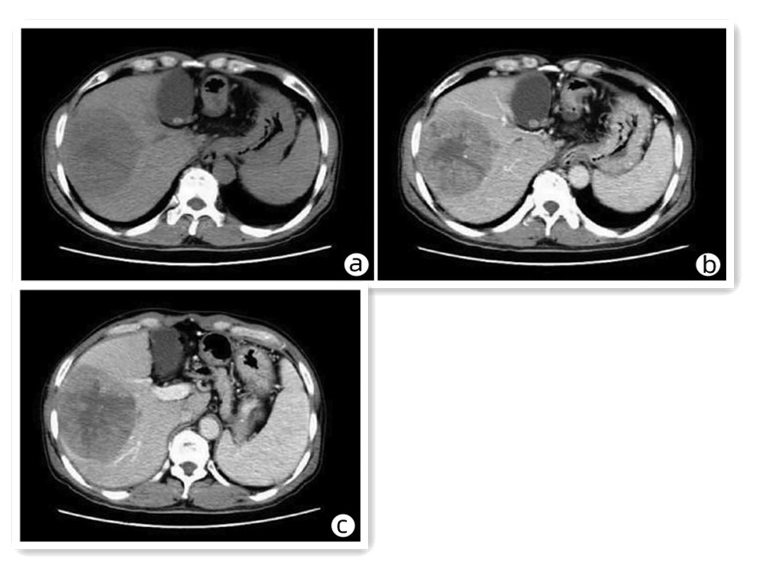

先天性左肝缺如合并肝细胞癌1例报告

王海林, 李敬东, 武国

2023, 39(6): 1408-1410. DOI: 10.3969/j.issn.1001-5256.2023.06.023

摘要(836) HTML (197) PDF (2003KB)(59)

摘要: